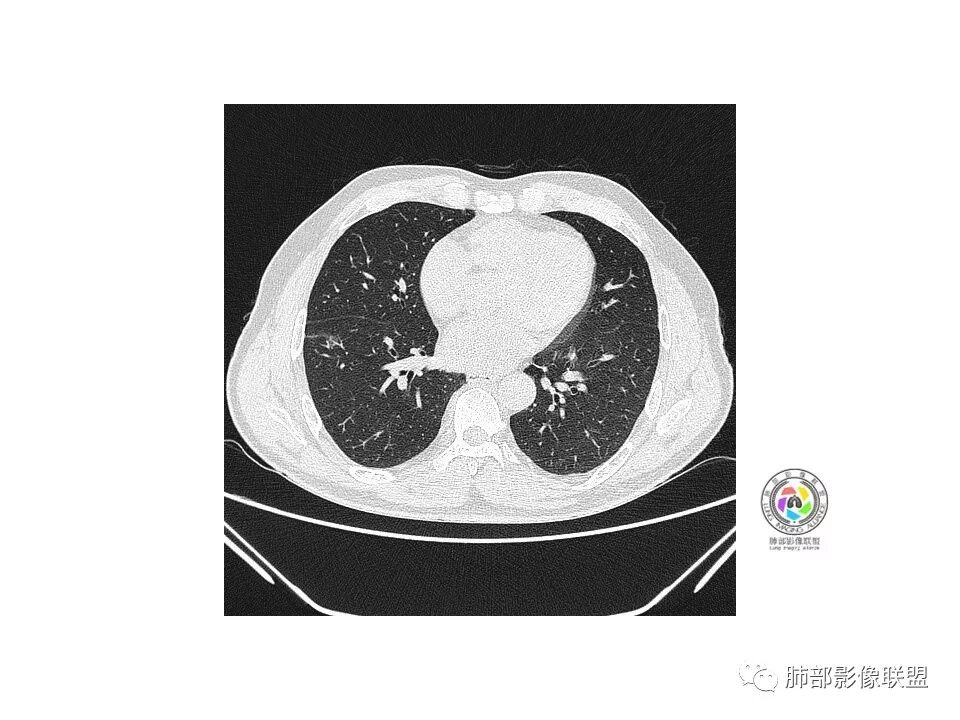

右肺下叶见边界清晰混合磨玻璃密度影,目测内见实性结节小于5mm,有浅分叶,前缘小叶间隔阻挡,月牙铲?胸膜牵拉,老年患者,MIA可能,鉴别炎性病变,抗炎后复查

患者老年男性,以咳嗽 、咳痰3天就诊,胸CT:右肺下叶前基底段mGGO,内可见血管形态改变,细支气管扩张,病灶边界清,边缘可见月牙铲。考虑恶性,腺癌?但建议先抗炎治疗后复查

老年男性、咳嗽咳痰三天,右下前基底段GGN,血管影增多,伴类似的树芽,边缘稍模糊,考虑结核。

右肺下叶磨玻璃结节,密度不均,边缘收缩,胸膜牵拉,考虑炎性,建议复查,除外腺癌。

右肺下叶混合磨玻璃结节,边缘清晰,浅分叶,月牙铲,胸膜牵拉,血管进入,考虑MIA可能,鉴别炎性病变

磨玻璃结节,边缘清楚,浅分叶,月牙铲,考虑腺癌可能,抗炎后复查。

右肺下叶混合磨玻璃密度结节影,局部胸膜牵拉,月牙铲,考虑腺癌

磨玻璃小结节,有明显收缩性表现,胸膜凹陷,考虑腺癌

患者老年男性,咳嗽  咳痰3天就诊。胸部CT:右肺下叶前基底段混合磨玻璃结节,边缘清楚,可见毛刺、胸膜牵拉、血管集束、月牙铲征象。综合考虑微浸润腺癌可能大。

右肺下叶前基底段混合磨玻璃结节,边界清,浅分叶,胸膜牵拉,月牙铲,血管进入,考虑:微浸润腺癌可能性大,抗炎后复查。

老年男性,右下叶孤立ggo,先抗炎2-3周复查,无变化→切,小了→炎性

40岁以上男性,孤立混合磨玻璃,边界清楚,分叶,胸膜凹陷,血管集束、穿行,考虑腺癌。

右肺下叶孤立混合磨玻璃结节,隐约细小毛刺,似有月牙铲,胸膜稍牵拉,考虑MIA(微浸润腺癌)可能,常规飞一下。